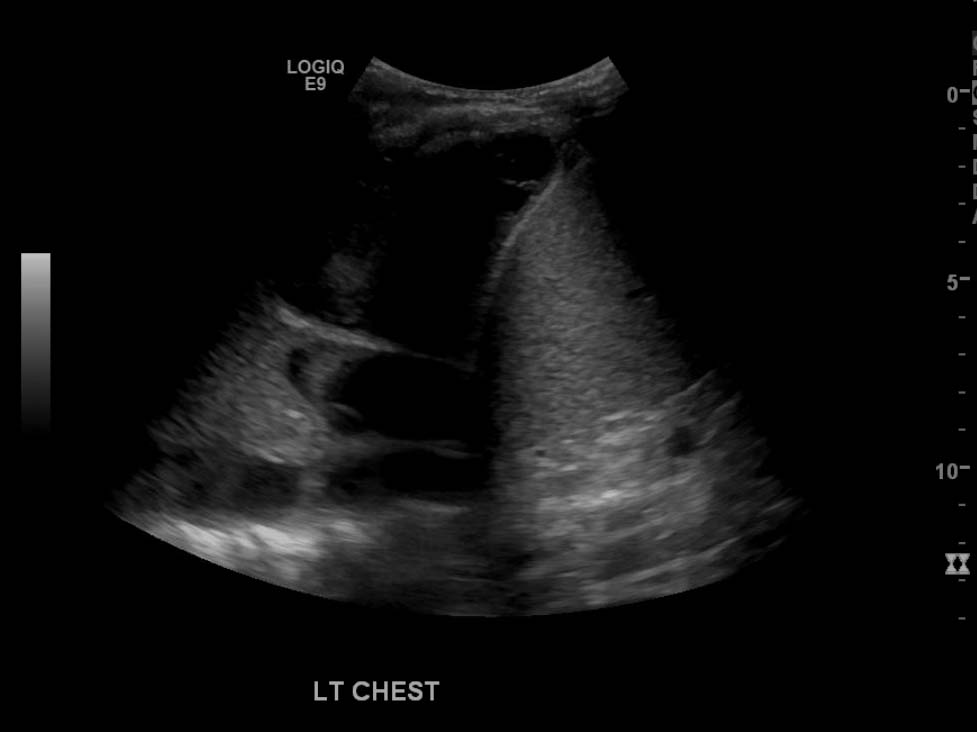

- Large, complex, multiseptated left pleural fluid collection

- Adjacent airspace consolidation in the left lung with air bronchograms

Pneumonia and empyema

Large, complex, multiseptated left pleural fluid collection with adjacent airspace consolidation, concerning for pneumonia and empyema. No discernible right pleural effusion.

- Worry about a complicated effusion (which may represent empyema, hemothorax, or malignant effusion depending on the clinical scenario) if the fluid collection has hyperechoic areas or if it contains internal septations

- As the lung fills with fluid, the only remaining air is in the bronchi, which produces air bronchograms – these appear as punctate and linear echogenic foci within the lung (see annotated image #3)

- Also, when densely consolidated, the lung becomes more discretely visible and takes a liver-like appearance, referred to as “hepatization”

- Pneumonia is an airspace filling process, so the size of the hepatized lung relative to the adjacent pleural fluid collection is often larger in pneumonia than in atelectasis